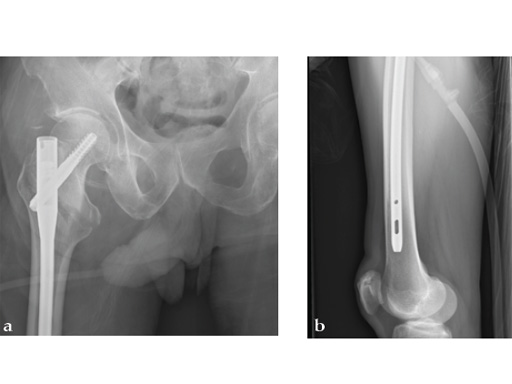

72-year-old female who sustained a closed intertrochanteric fracture in a car accident. The fracture was classified as an 31-A3-1. There were no other injuries reported.

Case provided by Cliff Turen, Macon, USA